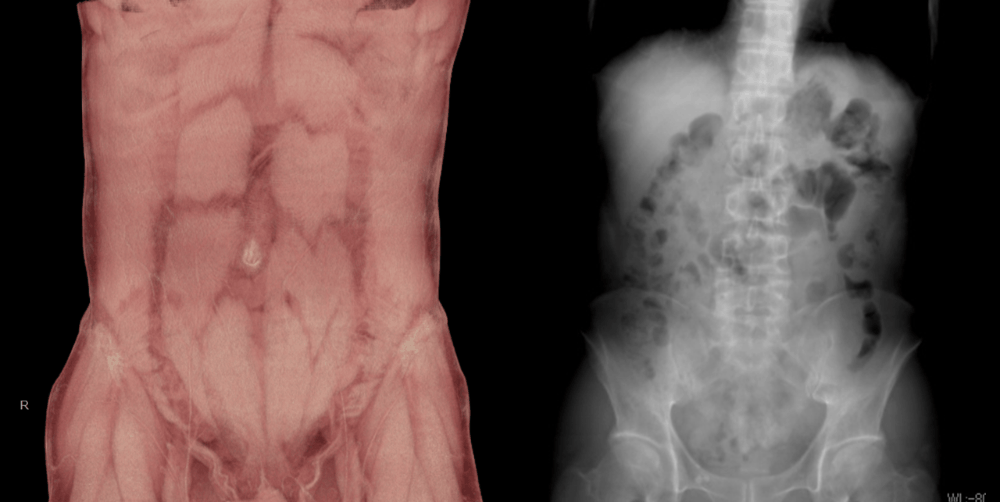

CT

当院ではGEヘルスケア製Revolution Maximaを設置しています

CTはX線とコンピュータを用いて、体の内部を自由な角度の断面で画像化できる検査で、頭部・胸部・腹部に加え、血流や骨などの詳細な情報を得ることができます。CTの高精度な画像を診断に用いることは、様々な病気の早期発見や治療後の経過観察に役立っています。検査は短時間で終了するため、患者様の負担も少ないです。また、実際の撮影したデータの統計を元にして、当院で行われた検査の被ばく線量が適正であることを年に2回検討し、線量低減対策に取り組んでいます。